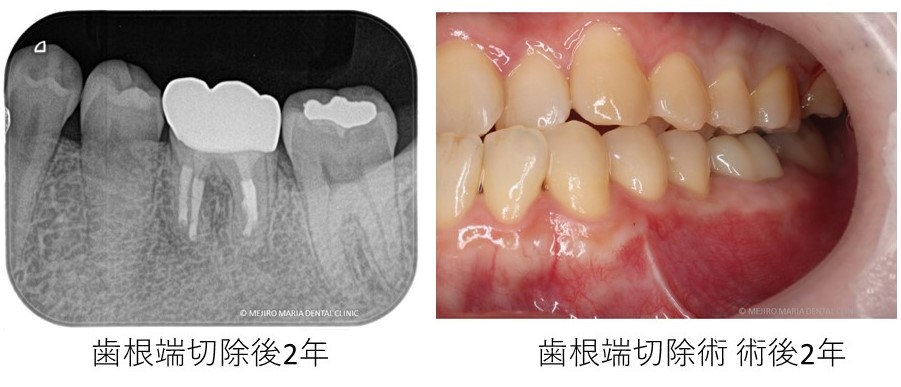

<2022年2月追記>

2年間術後1年おきに経過観察を行った結果、歯根端切除術後に違和感や腫れはなく良好な治癒を確認しております。

この患者様は前医にて2年以上、左下6番の根管治療を毎週行っていた症例です。通院のかいもなく最終的には抜歯を宣告され当院を受診されました。

当院にて完璧な環境下で再根管治療を行いましたが、サイナストラクト(瘻孔・フィステル)の消失までは至りませんでした。これは、「根管治療の限界」と言われます。

複雑な解剖学的形態であるが故に洗浄が行えないことや、時に細菌が根尖孔外(根の外側)で感染を広げ根管治療(中からの治療)では感染源を除去することが難しい場合があるからです。そのような難症例でも、根管治療に引続き歯内療法外科(歯根端切除術)を行うことで根尖性歯周炎を治癒に導くことが可能です。